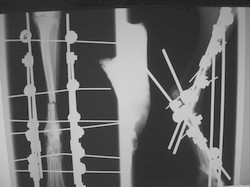

PRÁCTICAS CURSO DE FIJACIÓN EXTERNA PERFECCIONAMIENTO.

Artrodesis tarso.